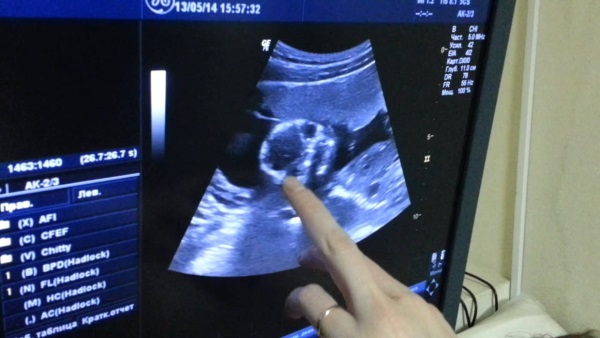

- вес плода (определяется с помощью ультразвукового исследования);

На втором этапе беременности женщина начинает ощущать первые шевеления своего малыша, а также, в ряде случаев, после планового ультразвукового исследования уже может узнать его пол (во втором триместре половая система ребенка уже полностью формируется, что позволяет врачу-узисту визуально предположить, кого ждет женщина – мальчика или девочку).

Развитие плода по неделям: На 8-й неделе беременности у плода уже формируются основные органы, такие как сердце, легкие и почки. На 20-й неделе можно уже определить пол ребенка с помощью УЗИ, а на 28-й неделе плод начинает активно реагировать на звуки и свет, что свидетельствует о развитии его сенсорных систем.